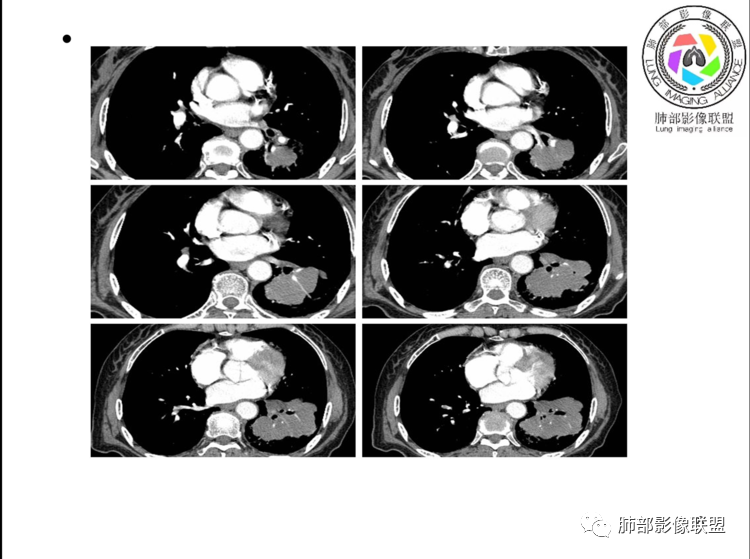

团片,内有支气管扩张,血管飘浮,不均匀强化,累膈肌似侵及脾脏,考虑恶性,淋巴瘤?肉瘤?

左肺下叶团块,边缘膨隆分叶,支气管部分阻塞、部分进入扩张,密度不均,延迟强化,血管走行正常,病灶与左侧膈肌分界不清。考虑恶性肿瘤:1淋巴瘤;2肉瘤样癌。

左肺下叶巨大实性肿块,支气管进入后阻塞,血管走行自然,增强中度均匀强化,无明显坏死。与膈肌分界不清,是否有侵犯导致腹痛症状?

考虑恶性肿瘤,低分化腺癌或者淋巴瘤?

老年女性,上腹部疼痛为主诉,CT所示左肺下叶肿块,左肺下叶支气管变窄,局部阻塞,病灶可见分叶,内见僵硬稍扩张的支气管,增强扫描病灶中度强化,内见血管造影征,首先考虑恶性病变,腺癌和淋巴瘤需要考虑,转移瘤待排除。

老年女性,以上腹痛就诊,左肺下叶团块影,边界清,可见分叶,延迟强化,内未见明显坏死,可见支气管充气扩张,血管走形自然,考虑淋巴瘤

老年女性,上腹痛就诊,CT可见左肺下叶巨大肿块,支气管进入后变窄堵塞,血管走行自然,内可见稍扩张支气管,增强均匀强化,与膈肌分界不清,考虑为恶性,淋巴瘤或腺癌可能

老年女性,左肺下叶软组织肿块,密度较均匀,边缘膨隆分叶,临近支气管截断,肿块内可见支气管穿行,与膈肌分界不清,增强后动脉期轻度均匀强化,静脉期呈渐进性强化,欠均匀,内血管走形如常,可见血管漂浮,整体感觉病灶偏软,考虑淋巴瘤可能大,鉴别腺癌。

患者老年女性,上腹部疼痛一周,无呼吸道症状,查体无阳性体征。血常规、尿常规、肝肾功能正常。肿瘤标志物CA125稍升高。胸部CT:左肺下叶肿块灶,边缘欠光滑,边界欠清楚,见分叶、血管集束征象,内见支气管扩张,增强中度强化,见血管漂浮征象。综合考虑恶性病变,淋巴瘤可能大,鉴别肺癌。

左下肺不规则巨大肿块,下叶支气管部分阻塞,部分扩张,与左侧膈肌分界不清,增强延迟强化,可见血管造影征,考虑恶性,淋巴瘤可能大,鉴别腺癌

老年女性,上腹部疼痛一周,肿标CA125升高。胸部CT:左肺下叶巨大肿块,分叶,密度不均,与左膈肌分界不清,内见枯枝征,部分支气管进入后截断,增强中度延迟强化,见血管漂浮征。胃壁不均匀增厚。考虑:恶性肿瘤病变伴阻塞性炎症,淋巴瘤?腺癌转移?鉴别TB、隔离等。

老年女性,左下肺大肿块、深分叶,考虑恶性肿瘤。纵隔肺门淋巴结无明显肿大,不支持小细胞癌;支气管进入后截断、肿块破坏力不强,不支持鳞癌,内部血管走行自然,不怎么支持腺癌,支持淋巴瘤;肉瘤似乎内部很少见支气管。

左肺下叶实变影,形态尚规则,外缘欠光滑,呈膨胀性生长,叶裂推移,近段支气管穿行,支气管略扩张,平扫密度均匀,增强后可见穿行血管,老年女性,无感染症状,实验室检查肿瘤标志物高,考虑恶性:1:淋巴瘤;2:腺癌;3:IMT

左下肺肿物,有分叶及血管飘浮征,定性恶性,无胸膜牵拉及毛刺,提示收缩力差,可排除腺癌。女性,肿块内坏死不明显(鳞烂心)不首选鳞癌。老年女性,血管飘浮,特别是膈肌受累首选淋巴瘤

定位,肺内,血管支气管穿行

定性,恶性,腺癌跟淋巴瘤鉴别

腺癌支持点就是常见病,发病率高,CEA高。不好解释血管穿行比较自然。病灶整体偏软,所以淋巴瘤放前面

考虑淋巴瘤!鉴别腺癌 首先看病灶恶性征象多,深分叶支气管截断,支气管感觉是受压闭塞,肺动脉显示良好,血管漂浮征!这么大肿瘤如果是鳞癌不可能没有坏死!腺鳞癌同样如此,肉瘤样癌同理,类癌、不典型类癌明显强化,而这例轻度延迟性比较均匀强化,淋巴瘤感觉是符合 特别是MALT

弥漫性大B细胞淋巴瘤